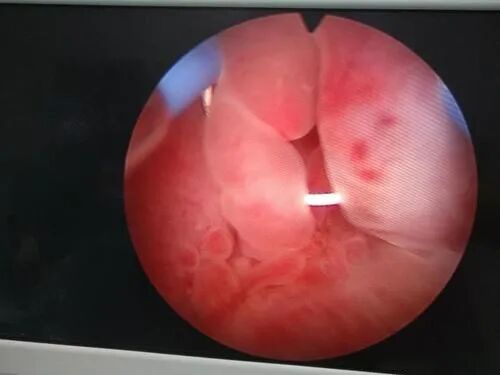

有报道称IVF失败史患者,尤其是反复移植失败(repealted implantation failure,RIF)患者,再次IVF前进行宫腔镜下EP切除术很必要。

③ 宫腔粘连(IUA)

子宫内膜基底部损伤后异常愈合的结果,其原因主要是宫腔感染、子宫内膜损伤等。

IUA破坏子宫内膜形态结构和功能完整性,造成宫腔狭小、畸形甚或封闭,损伤子宫内膜容受性,降低妊娠率,增加流产风险。